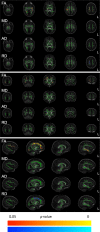

Methods: Nested cohort study within the Magnesium sulphate at 30 to <34 weeks' Gestational age Neuroprotection Trial (MAGENTA). Australian New Zealand Clinical Trials Registry ACTRN12611000491965. Mothers at risk of preterm birth at 30 to <34 weeks' gestation were randomised to receive either 4 g of magnesium sulphate heptahydrate [8 mmol magnesium ions], or saline placebo, when preterm birth was planned or expected within 24 h. Participating babies underwent diffusion tensor MRI at term equivalent age. The main outcomes were fractional anisotropy across the white matter tract skeleton compared using Tract-based Spatial Statistics (TBSS), with adjustment for postmenstrual age at birth and at MRI, and MRI site. Researchers and families were blind to treatment group allocation during data collection and analyses.

Findings: Of the 109 babies the demographics of the 49 babies exposed to magnesium sulphate were similar to the 60 babies exposed to placebo. In babies whose mothers were allocated to magnesium sulphate, fractional anisotropy was lower within the corticospinal tracts and corona radiata, the superior and inferior longitudinal fasciculi, and the inferior fronto-occipital fasciculi compared to babies whose mothers were allocated placebo (P < 0·05).